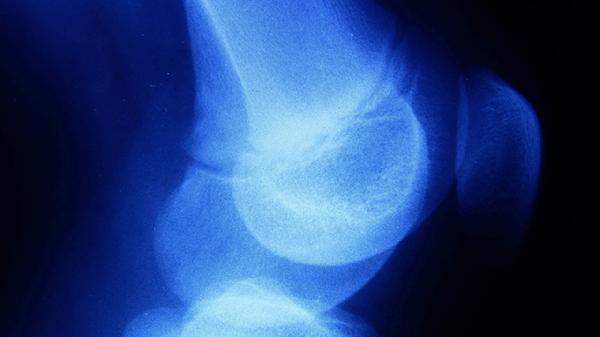

3、关节活动受限

中指骨膜炎可能导致关节活动受限,患者可能出现屈伸困难、握力下降等症状。关节活动受限可能与炎症引起的肿胀、疼痛等因素有关。患者应减少手指过度活动,必要时可遵医嘱使用支具固定。